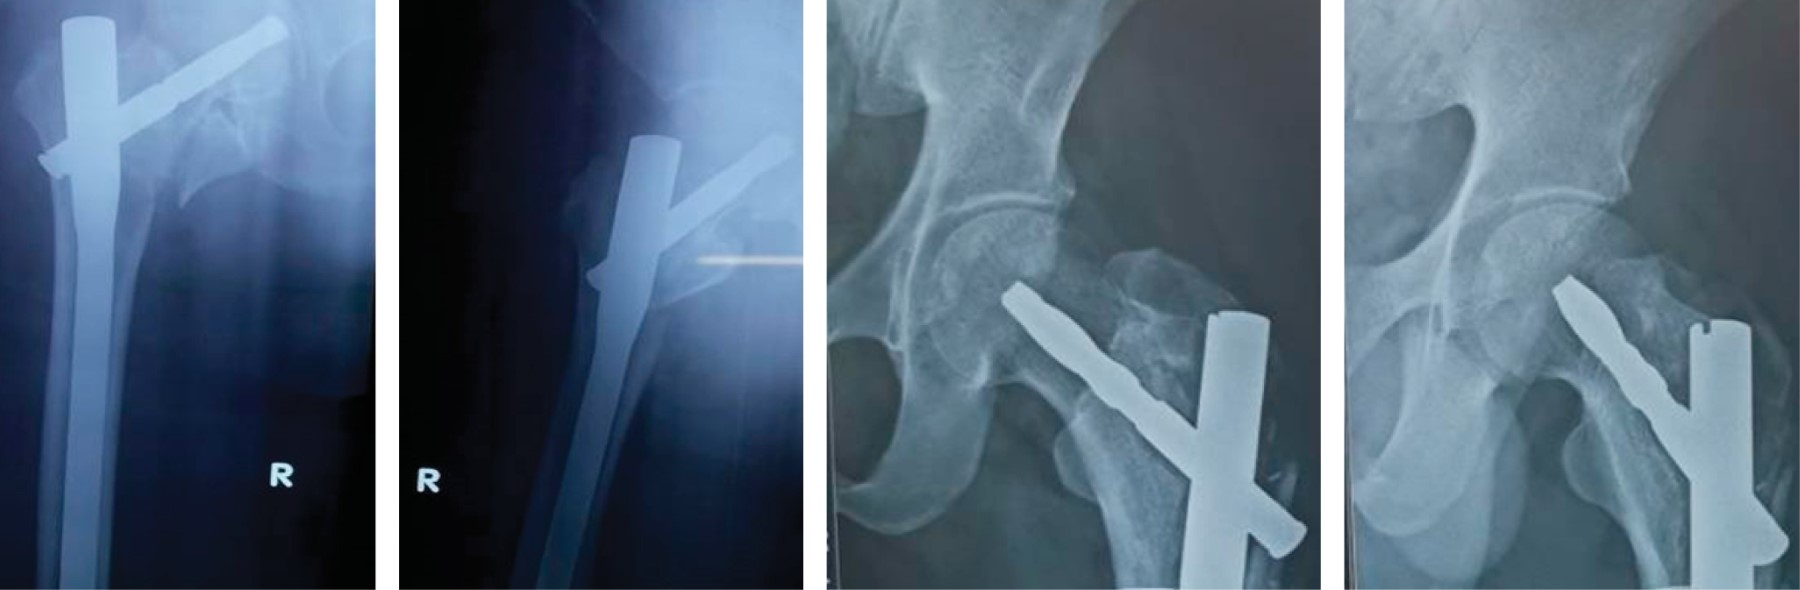

Implant related complications like screw back out (Figure 1), guide wire breakage (Figures 2 and 3), Z effect (Figure 4), TAD outliers (Figure 5) were more in PFN group whereas lateral screw protrusion, locking mechanism failure and barrel disengagement was more in PFNA2 group as shown in Figures 6, 7, 8 and 9. Neck shaft valgus outliers are more common in PFN group (Figure 10).

Implant-related complications, such as screw back-out, guidewire breakage, and proximal protrusion, were more pronounced in the PFN group, whereas lateral screw protrusion and medial migration were notable in the PFNA2 group.24 Lateral screw protrusion was observed in four patients in the PFNA2 group and one patient in the PFN group at the final follow-up in our study. Hu et al suggested a morphological mismatch in the Asian population between the proximal fragment of PFNA2 and the greater trochanter, leading to post-operative lateral trochanter pain.24